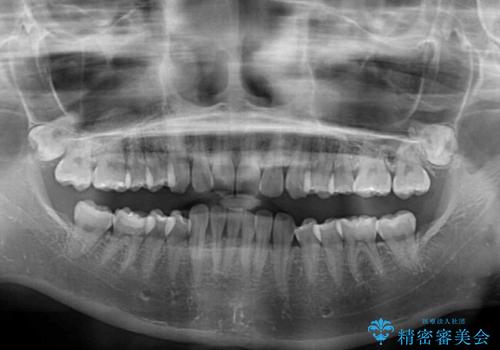

- 口元の深い咬み合わせ(ディープバイト)を気にして来院された患者様です。

インビザラインによる上下歯列の遠心移動(後方移動)により、口元のデコボコとディープバイトを改善することとしました。

下顎左右の犬歯とその後ろにある第一小臼歯、計4歯がシミュレーション通りに動かずディープバイトがなかなか改善されませんでした。

マウスピースの再製作を何度か行いましたがうまくいかないため、部分的にワイヤー矯正を併用することを提案しました。しかし、最も気になっていた前歯のデコボコはきれいに改善されたため、これ以上治療を希望されず、治療を終了することとしました。(今後気になった際には再開する予定です)